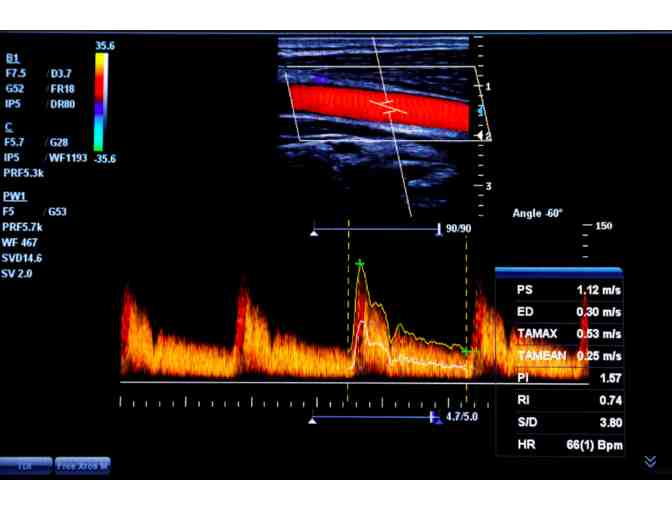

Heart disease is the leading cause of death for men and women in the United States. Stroke is the 5th leading cause of death. Preventive health screenings, which are also non-invasive, can identify risk factors that can lead to cardiovascular disease and stroke. This allows people to understand their risk of developing a condition before symptoms are present so that they can take action. As part of this screening, the individual will receive a limited EKG and a carotid ultrasound to assess plaque buildup.